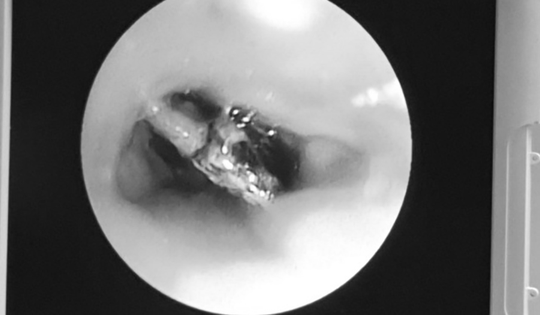

Bé trai 7 tuổi xẹp phổi trái, bác sĩ gắp ra thứ "đáng sợ" bên trong

16/02/2026 02:00

Bé trai 7 tuổi ở Nghệ An nhập viện trong tình trạng khó thở, tím tái. Bác sĩ ngay lập tức lấy thành công mảnh nhựa sắc nhọn, kịp thời ngăn suy hô hấp và biến chứng nặng.